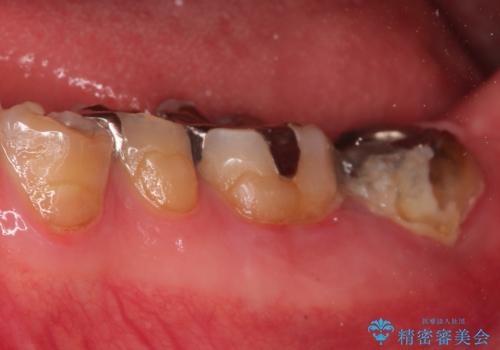

今回の症例は遠心根を保存するメリット・デメリットを患者さんと話し合い、治療を進めております。

条件が少しでもよくなる様に、再生治療および確定外科を行い良好な歯周状態でオールセラミッククラウンを装着しております。